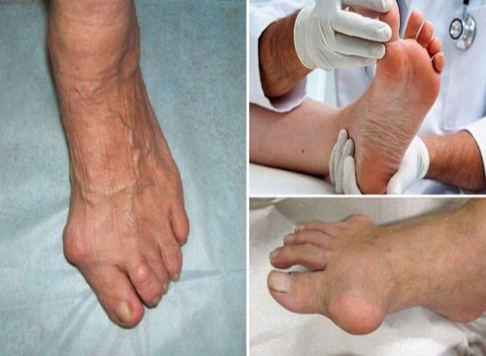

무지외반증("hallux valgus”)이란?

무지외반증은 발가락 통증을 일으킬 수 있는 특정한 상태입니다. 이는 발가락으로 통증을 유발할 수 있는 신경 주위의 조직이 두껍고 확장되는 경우 발생합니다. 이는 특히 세 번째와 네 번째 발가락 사이의 발의 앞부분에서 심한 불편함을 초래할 수 있습니다.

무지외반증의 증상

무지외반증의 흔한 증상은 다음과 같습니다.

- 발 앞부분에서 날카로운, 화끈한 통증.

- 영향을 받는 발가락에서의 저림 또는 따끔거림.

- 신발 안에 돌 또는 물체가 있다는 느낌.